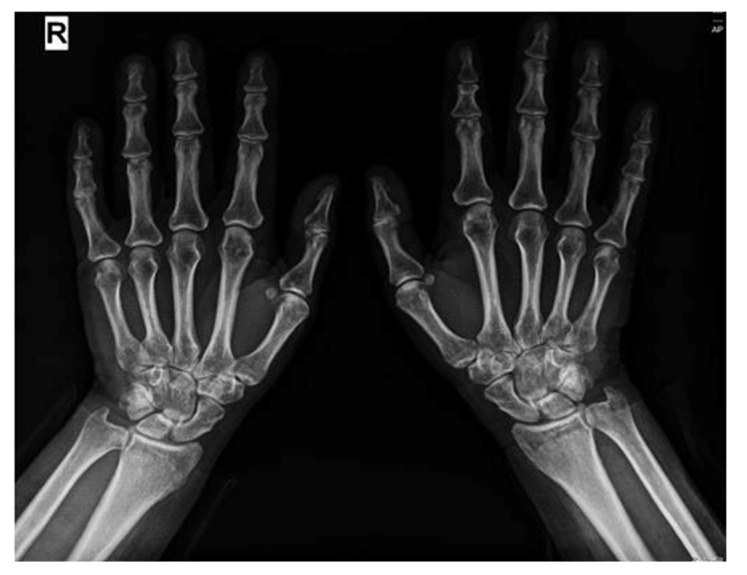

背景和临床意义:抗合成酶综合征(ASyS)是一种罕见的自身免疫性疾病,其特征是存在抗氨基酰基-t核糖核酸(RNA)合成酶自身抗体,通常与间质性肺疾病(ILD)、炎症性肌病和关节炎有关。其他临床特征可能包括雷诺现象和“机械师之手”。在抗合成酶抗体中,抗pl -12与显性或孤立性ILD明显相关,并且可能在没有临床明显肌炎的情况下发生,从而使及时诊断复杂化。病例介绍:我们报告一位45岁的非吸烟女性患者,既往诊断为血清阴性类风湿性关节炎(RA),出现进行性呼吸困难、干咳和恶心症状。高分辨率计算机断层扫描显示非特异性间质性肺炎(NSIP)模式。尽管肌酸激酶和乳酸脱氢酶水平正常,血清学检查显示抗pl -12和抗ro52抗体阳性,支持抗合成酶综合征的诊断,无肌炎,符合conors和Solomon的ASyS诊断标准。皮质类固醇和环磷酰胺治疗可诱导临床和呼吸功能改善,而硫唑嘌呤用于维持。结论:该病例强调了抗合成酶综合征的临床异质性,并强调了在没有肌炎的情况下,抗pl -12相关ILD所带来的诊断挑战。重要的是,该研究表明,在已有风湿病诊断的患者中,非典型肺部表现的出现需要重复血清学评估,以评估ASyS和其他自身免疫性疾病。早期诊断和免疫抑制治疗对优化预后至关重要。

Background and Clinical Significance: Antisynthetase syndrome (ASyS) is a rare autoimmune entity defined by the presence of anti-aminoacyl-t ribonucleic acid (RNA) synthetase autoantibodies and classically associated with a triad of interstitial lung disease (ILD), inflammatory myopathy, and arthritis. Additional clinical features may include Raynaud's phenomenon and "mechanic's hands". Among antisynthetase antibodies, anti-PL-12 is notably associated with predominant or isolated ILD and may occur in the absence of clinically evident myositis, thereby complicating timely diagnosis. Case Presentation: We are presenting a 45-year-old non-smoking female patient with a prior diagnosis of seronegative rheumatoid arthritis (RA) who developed progressive dyspnea, dry cough, and sicca symptoms. High-resolution computed tomography revealed a nonspecific interstitial pneumonia (NSIP) pattern. Despite normal creatine kinase and lactate dehydrogenase levels, serological work-up revealed positive anti-PL-12 and anti-Ro52 antibodies, supporting a diagnosis of antisynthetase syndrome without myositis, fulfilling the diagnostic criteria for ASyS per Connors and Solomon. Treatment with corticosteroids and cyclophosphamide induced clinical and functional respiratory improvement, while azathioprine was initiated for maintenance. Conclusions: This case underscores the clinical heterogeneity of antisynthetase syndrome and highlights the diagnostic challenge posed by anti-PL-12-associated ILD in the absence of myositis. Importantly, it demonstrates that in patients with pre-existing rheumatologic diagnoses, the emergence of atypical pulmonary manifestations warrants repeat serologic evaluation to assess ASyS and other autoimmune conditions. Early diagnosis and immunosuppressive treatment are essential to optimize outcomes.